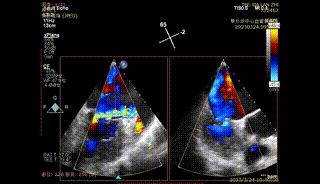

据心外科王圣教授介绍,本次手术在纯超声引导环境下进行,术中患者心脏不停跳,仅需在肋间开一小口,具有低外科损伤与零辐射的特点。该患者为二尖瓣C2区反流,P3脱垂,后叶较短,瓣叶质地欠佳,通过植入一枚ValveClampIIIf型夹子后反流基本消失,导管时间40分钟。术后24H患者脱机转入普通病房,术后48H患者下床活动,目前患者状态良好。

【二尖瓣相关参数】二尖瓣重度反流(继发性:Carpentier II型);A3:21mm P3:13mm,MVOA:5.3cm²,P3脱垂连枷,3区病变,瓣叶质地欠佳。

术前反流

反流基本消失